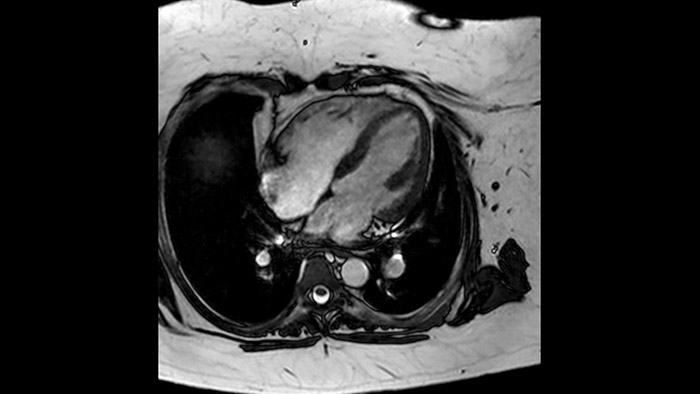

Diagnostic and prognostic utility of cardiac MR is increasing. Assess the anatomy and function of the heart using cine acquisitions, acquire information about perfusion and viability of the cardiac tissue, visualise potential edema with black blood sequence, access and even quantify tissue characterisation with CardiacQuant.

IntelliSpace Portal MR Caas5,6 Strain7 assists in patient diagnosis and monitoring by providing global strain parameters such as global longitudinal strain (GLS), global circumferential strain (GCS), and global radial strain (GRS), using short and long axis MR images, as well as describing the myocardium deformation- such as shortening, thickening, and lengthening during the cardiac cycle.